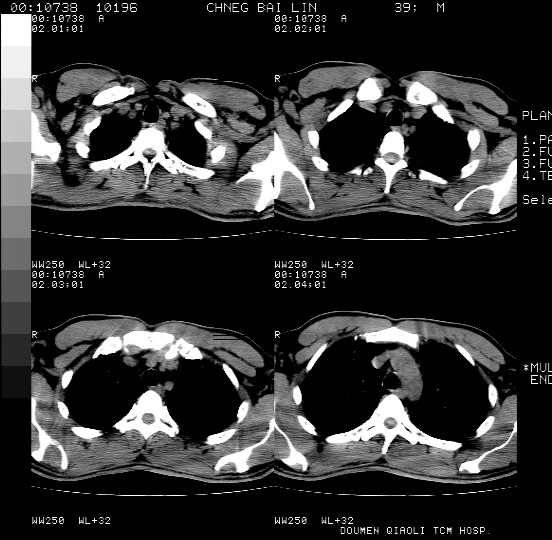

男,39岁。10天前自觉感冒,曾输液一次内容不详曾有吸毒史。现有咳嗽、咳痰胸闷。

双肺弥漫性网状、磨玻璃样病灶,边界不清。有吸毒史。首先考虑机遇性肺部感染。

两肺弥漫分布的网状毛玻璃状阴影,边缘模糊不清,纵隔未见明显淋巴结肿大

诊断:机遇性肺部感染